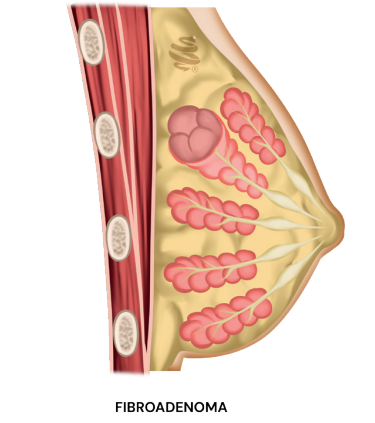

Fibroadenoma

É a lesão nodular mais comum. Apresenta-se como um nódulo fibroelástico, móvel e bem delimitado.

- Comportamento: É um hormônio dependente, podendo crescer na gestação e lactação, e evoluir na menopausa. Geralmente estabiliza entre 2 e 3 cm.

- Risco: Não eleva o risco para câncer de mama.

- Conduta: Acompanhamento clínico na maioria dos casos. A cirurgia é reservada para nódulos grandes (>2-3 cm), sintomáticos ou com crescimento progressivo.